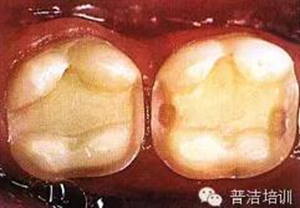

三、牙體預(yù)備完成,,邊緣預(yù)備短斜面(45度),短斜面這點(diǎn)很多書上沒具體說,想想還是有必要的,但在金屬嵌體和瓷嵌體就沒必要了。其實(shí)預(yù)備這一步驟沒什么高深莫測(cè)的,多加訓(xùn)練,端正態(tài)度就可以。

四、如果在預(yù)備過程中,有比較明顯的倒凹存在時(shí),可以在軸壁以及軸髓線角處涂一層蠟,并可作為樹脂水門汀預(yù)留在空間,但不可涂抹過多。